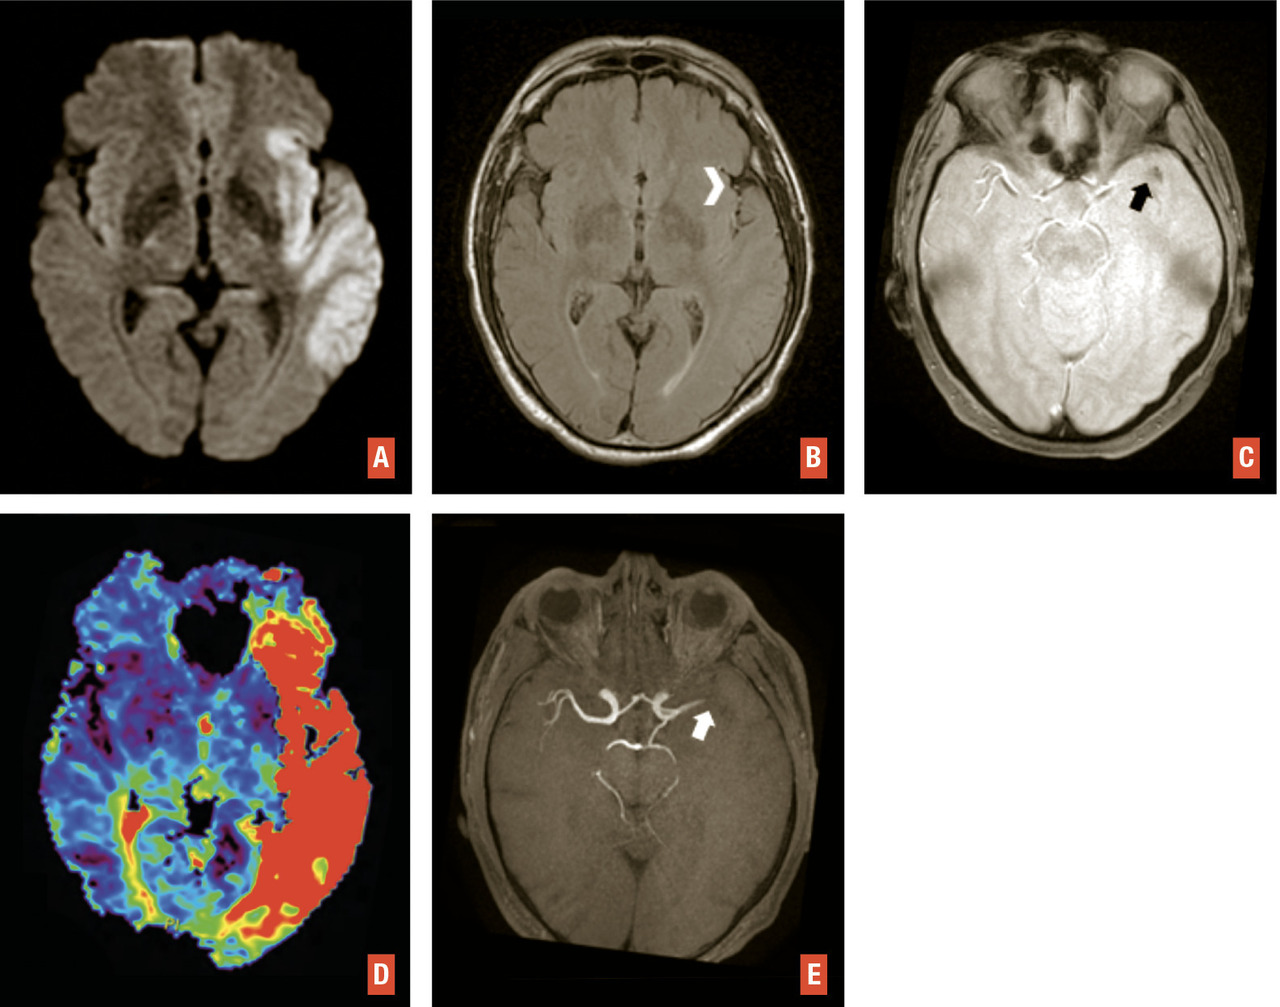

L’IRM est l’examen recommandé en France, si le plateau technique le permet sans retarder la prise en charge, et en dehors des contre-indications. Elle a une excellente sensibilité et spécificité pour détecter l’ischémie cérébrale aiguë. Un protocole standardisé est réalisable en moins de 10 minutes sans retarder la décision thérapeutique3 avec quatre séquences clés (– la séquence de diffusion pour détecter des lésions ischémiques récentes, en hypersignal avec baisse du coefficient apparent de diffusion, traduisant la restriction des mouvements des molécules d’eau secondaire à l’œdème cytotoxique. Bien que plus sensible que la tomodensitométrie, de rares faux négatifs peuvent s’observer en séquence diffusion en cas de lésion de petite taille, notamment de la fosse postérieure, d’examen très précoce ou de déficit transitoire ;

– la séquence de susceptibilité magnétique (T2* ou SWI) pour détecter un hématome,1 des séquelles hématiques ou une transformation hémorragique de lésions ischémiques, en particulier après traitement de recanalisation. Le thrombus artériel apparaît en hyposignal artériel linéaire ou curviligne en T2*, dont la sensibilité varie selon la composition du caillot, sa taille et le type de séquence utilisée ;

– la séquence FLAIR, qui permet d’apprécier l’étendue de la leucopathie vasculaire et les séquelles d’infarctus anciens, de dater l’infarctus (classiquement non visible avant 3 heures),1 de rechercher des hypersignaux vasculaires, en rapport avec des ralentissements vasculaires dans les artères collatérales en aval de l’occlusion ;

– l’angiographie par résonance magnétique (angio-IRM) 3D temps de vol du polygone de Willis (sans injection) afin de rechercher une occlusion ou une sténose des artères intracrâniennes. La séquence de perfusion T2* peut également être réalisée. Comme en tomodensitométrie, elle permet d’apprécier le risque d’extension de l’infarctus (« mismatch » perfusion-diffusion) et de décider d’un traitement de recanalisation dans des situations particulières (heure de début des symptômes inconnue, délai tardif)1 [

Ils représentent près de 20 % des suspicions cliniques d’AVC. L’IRM est plus performante que la tomodensitométrie pour distinguer un infarctus d’une pathologie non vasculaire. Les trois principaux diagnostics différentiels sont : déficits post-critiques, aura migraineuse, déficit « anorganiques » et, plus rarement, hypoglycémie, tumeurs cérébrales… En IRM, les anomalies ne sont pas systématisées à un territoire artériel et il n’existe pas d’occlusion artérielle.4 L’IRM permet d’orienter rapidement vers ces diagnostics différentiels et de proposer une prise en charge adaptée dès le stade aigu (fig. 4 ).